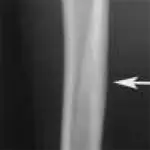

Figure 3A. This series represents an example of a probable fracture that cannot be seen on routine radiographs but that produces secondary signs that can be seen. Slight thickening of the caudal cortex of the tibia (arrow) is present in a dog with left hind limb lameness. The dog is an active, 3-yearold, castrated male black Labrador retriever having lameness for several months but with no prior history of lameness.

Figure 3B. Lameness was persistent, and cortical thickness progressed (arrow) over a 4-month period. Panosteitis might be considered in the differential diagnosis because of the several areas of uptake, although panosteitis does not typically start as a focal unicortical thickening of the bone in a 3-year-old dog.